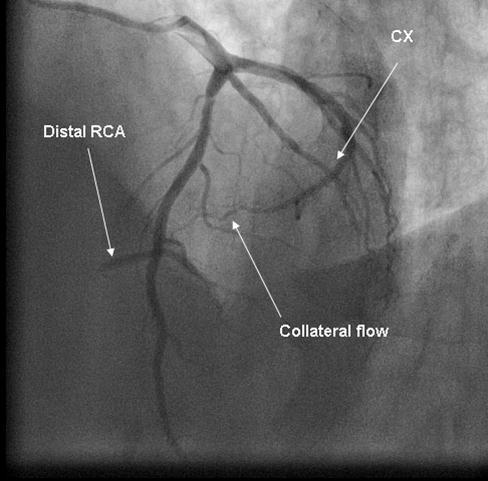

Coronary angiography was again performed. On injections into the left system, collaterals to the distal RCA were demonstrated (figure 1), arising from the left circumflex coronary artery (CX). Injections into the RCA demonstrated tight in-stent restenosis, (figure 2) and a drug eluting stent was successfully implanted. After the angioplasty, injections into the RCA were seen to retrogradely fill the CX (figure 3). The suspicion arose that maybe the left coronary artery had been inadvertently damaged during angiography, so the left coronary was again cannulated and injections performed, demonstrating entirely normal left main and CX arteries. However, the collateral flow that had previously been demonstrated from the CX to the RCA was no longer apparent. On review of the previous angiogram, it was noted that the RCA retrogradely filled the CX despite the original significant stenosis (figure 4). In essence, it became apparent that the bidirectional filling of the RCA from the CX and vice versa was in fact a direct continuity between the vessels and not collaterals, as free flow was noted from the RCA to the CX even when both arteries were completely patent.

Figure 1.Collateral flow from circumflex artery (CX) to right coronary artery (RCA) in cranial left anterior oblique view.